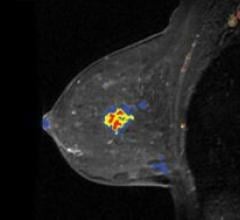

Confirma’s next-generation product for breast MRI includes a new customizable BI-RADS-centric user interface that ...

Hologic’s R2 Computer-Aided Detection (CAD) solutions reportedly give users the most sophisticated pattern recognition ...